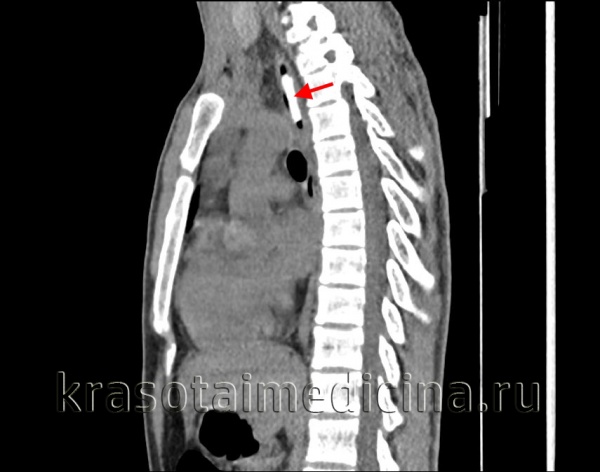

3. КТ при инородном теле пищевода:

• Позволяет обнаружить кости, обладающие даже незначительной рентгеновской контрастностью

• Может наблюдаться локальная эмфизема мягких тканей, отек, гематома, абсцесс; а также ИТ, перфорирующее стенку пищевода